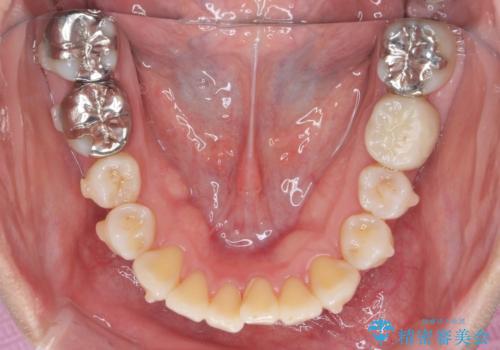

捻れた奥歯 突き出た前歯を治したい

- 出っ歯に見える前歯、捻れてしまった小臼歯の改善を求めて来院されました。

マウスピースでは改善の難しい小臼歯のねじれをまず部分ワイヤー矯正で改善し、その後マウスピース矯正で前歯の突出感を改善します。

時間はかかりましたが、捻れ、かみ合わせ、前歯の角度の改善が達成され満足いただくことができました。